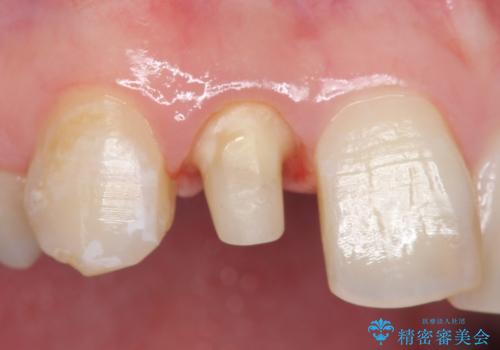

- 右上2番目の歯の被せ物と歯茎の間の継ぎ目が気になるといらっしゃった方の症例です。

再根管治療は希望されなかったため、クラウン除去後、オールセラミッククラウン(スペシャル)による補綴を行いました。

- オールセラミッククラウン(スペシャル)…¥130,000、仮歯…¥10,000、ファイバーコア…¥20,000費用は治療当時の料金となります